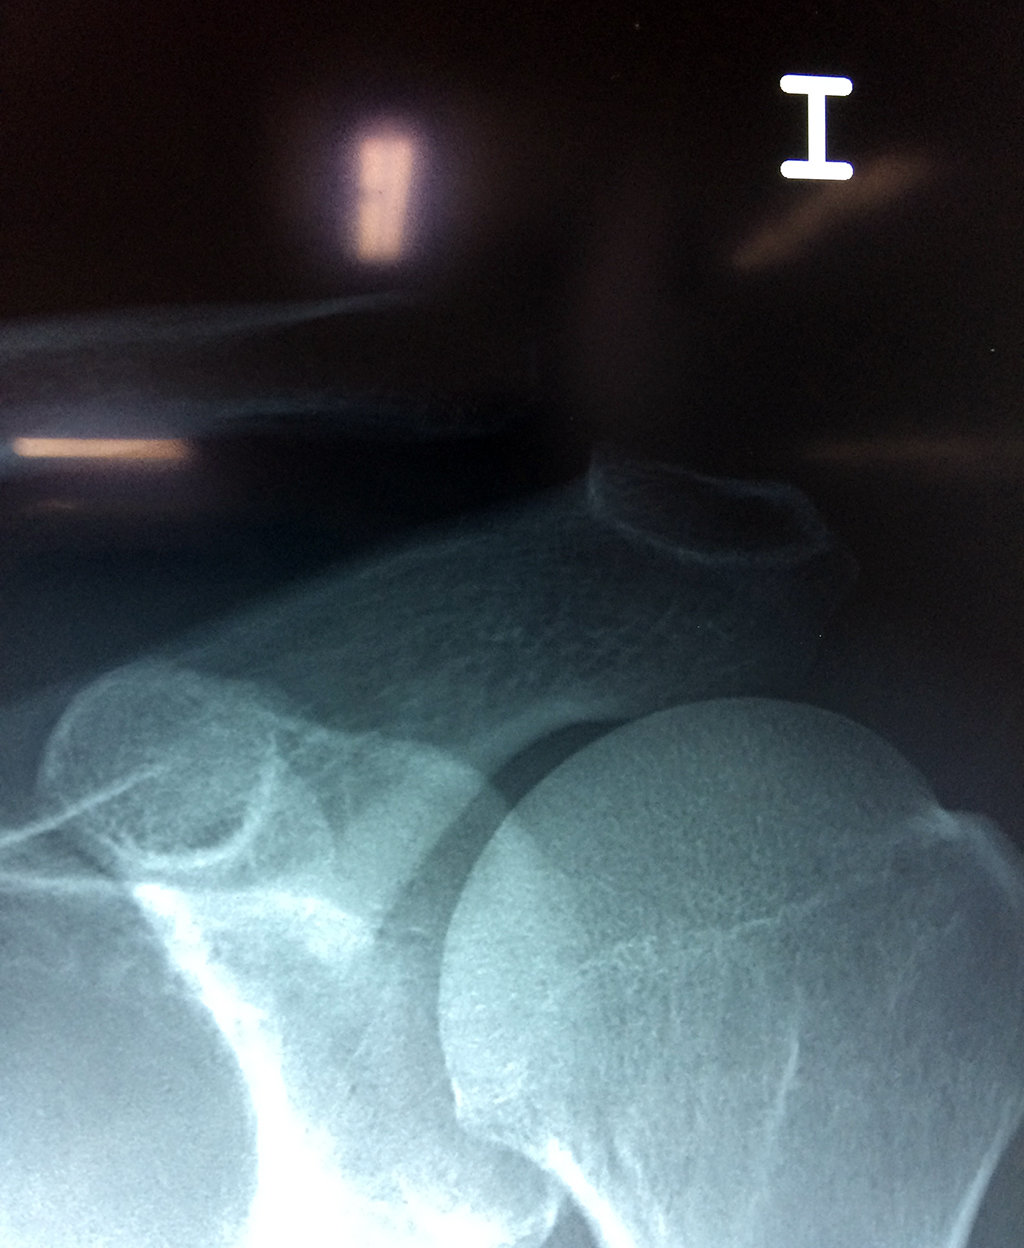

Cirugías de Húmero - Clavícula

La clavícula es un hueso largo, con forma de "S" itálica, situado en la parte anterosuperior del tórax. Junto con la escápula forman la cintura escapular. Se puede palpar por toda su longitud y se extiende del esternón al acromion de la escápula, siguiendo una dirección oblicua lateral y posterior.